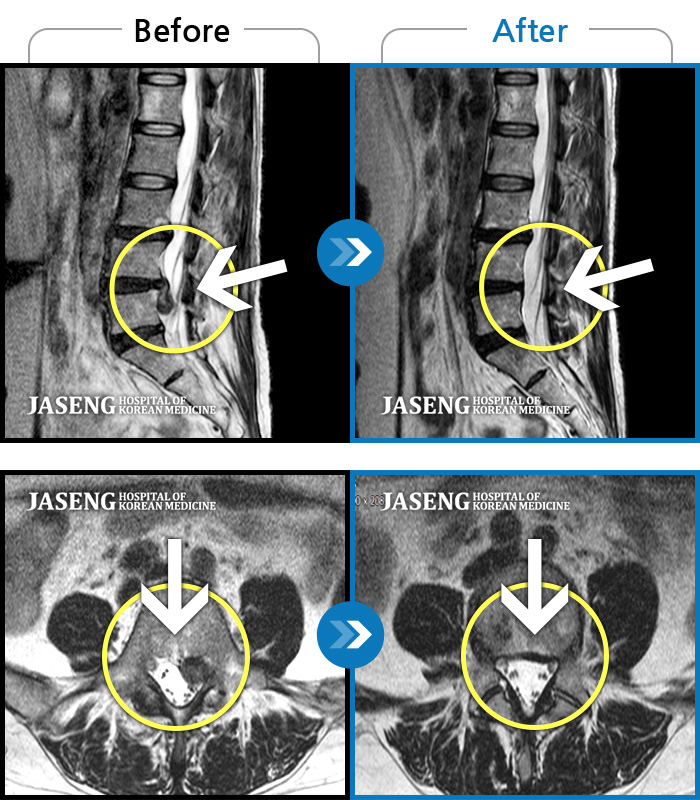

허리디스크

도움받은 사례

인천 · 조남훈 원장

재채기 하고 나서 다리에 힘이 안들어가요.

촬영시기

2021.11.10 ~ 2024.11.26

2024.12.04

조회수 442